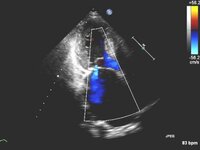

Apical 4-chamber view of 4+ (severe) mitral regurgitation and a large proximal isovelocity surface area

From the collection of Samir Kapadia and Mehdi H. Shishehbor